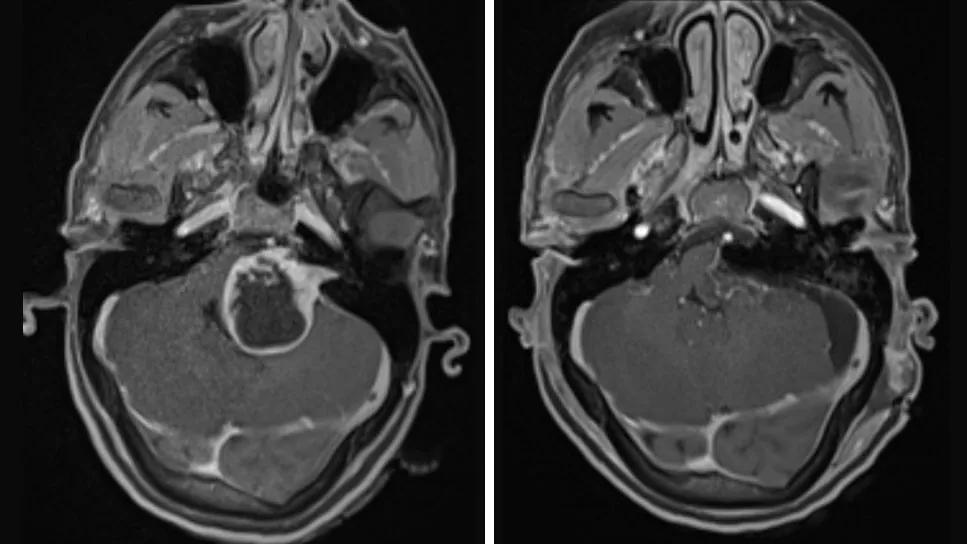

Vestibular Schwannoma pre- and post-operative CT scans

A postoperative MRI revealed complete gross resection of the tumor.